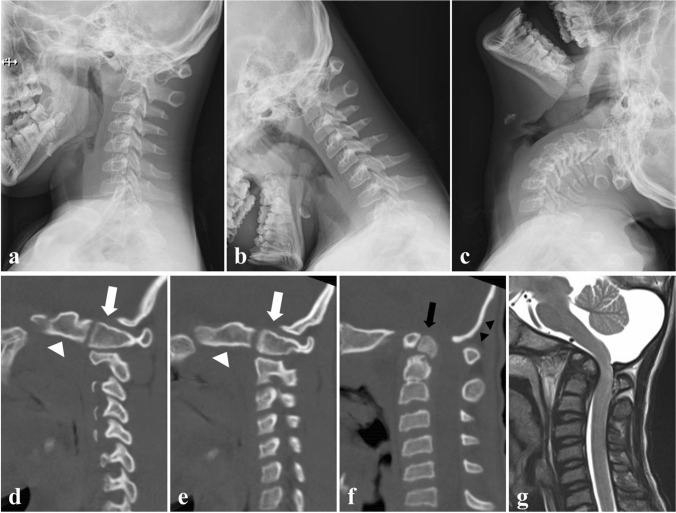

The patient first presented to our department at 3 years of age for abnormal cervical radiography findings. He was diagnosed with Down syndrome at birth. His family history was unremarkable. Radiography showed basilar invagination and kyphotic O-C2 alignment (Fig. 1a, b). Sagittal reconstruction computed tomography demonstrated that the bilateral occipital condyles were anteriorly displaced to the C1 lateral masses, forming vertical O-C1 joints (Fig. 1c, d). He had no history of trauma; therefore, this condition was diagnosed as congenital atlanto-occipital dislocation. We started an annual outpatient clinic follow-up because he showed no signs of myelopathy. At 13 years of age, the patient presented with progressive gait disturbance and difficulty sitting due to cervical myelopathy. Cervical radiography revealed a mobile atlantoaxial segment with basilar invagination and O-C2 kyphosis (Fig. 2a–c). Computed tomography revealed os odontoideum protruding into the foramen magnum with bilateral atlanto-occipital dislocation (Fig. 2d–f). Magnetic resonance imaging showed kyphotic alignment of the spinal cord with severe compression at the foramen magnum level (Fig. 2g).

Fig. 2.

Preoperative cervical spine images at 13 years old. a-c Dynamic lateral plain radiographs of the cervical spine showing atlantoaxial instability with basilar invagination and O-C2 kyphosis. d, e Parasagittal reconstruction computed tomography showing vertical O-C1 joints formed by anteriorly displaced bilateral occipital condyles (white arrow heads) and C1 lateral masses (white arrows). f Midsagittal reconstruction computed tomography demonstrated os odontoideum (black arrows) protruding into the foramen magnum and O-C2 kyphosis with a thinned central portion of the occipital bone (black arrow heads). g T2-weighted sagittal magnetic resonance imaging showing kyphotic alignment of the spinal cord with severe compression at the foramen magnum level